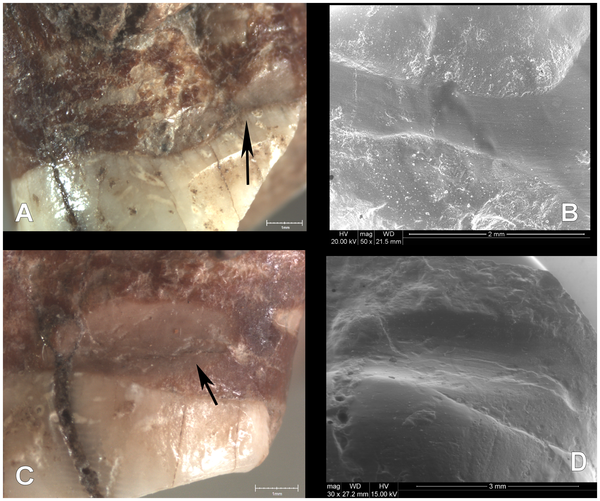

E a seguir veio a parte mais curiosa do estudo: na zona de contacto entre dois dentes, o primeiro pré-molar e o primeiro molar do lado superior esquerdo, a maxila apresenta sulcos bem visíveis. Ora, estes "sulcos interproximais" resultaram do uso frequente de um palito. “A localização, morfologia e tamanho dos sulcos coincidem com os sulcos interproximais encontrados nos dentes de outros fósseis”, refere a equipa o artigo científico.

“Para tentar aliviar o incómodo causado pela doença periodontal, com uma importante inflamação das gengivas, que sangravam frequentemente, este indivíduo utilizava um palito de forma sistemática”, diz por sua vez Marina Lozano, do instituto catalão, citada no comunicado. “É muito possível que lhe tenham ficado bocados de alimentos entre as raízes dos dentes e as gengivas, e que tentasse tirar esses restos de comida para aliviar a dor”, refere a investigadora.

“Além disso, a inflamação das gengivas por si só também provoca a sensação de ter um corpo estranho sem que este exista. Tal como fazem hoje muitos doentes de periodontite, isto faria com que aquele Neandertal usasse um palito com mais frequência e intensidade, o que lhe provocou os sulcos interproximais”, acrescenta Marina Lozano.